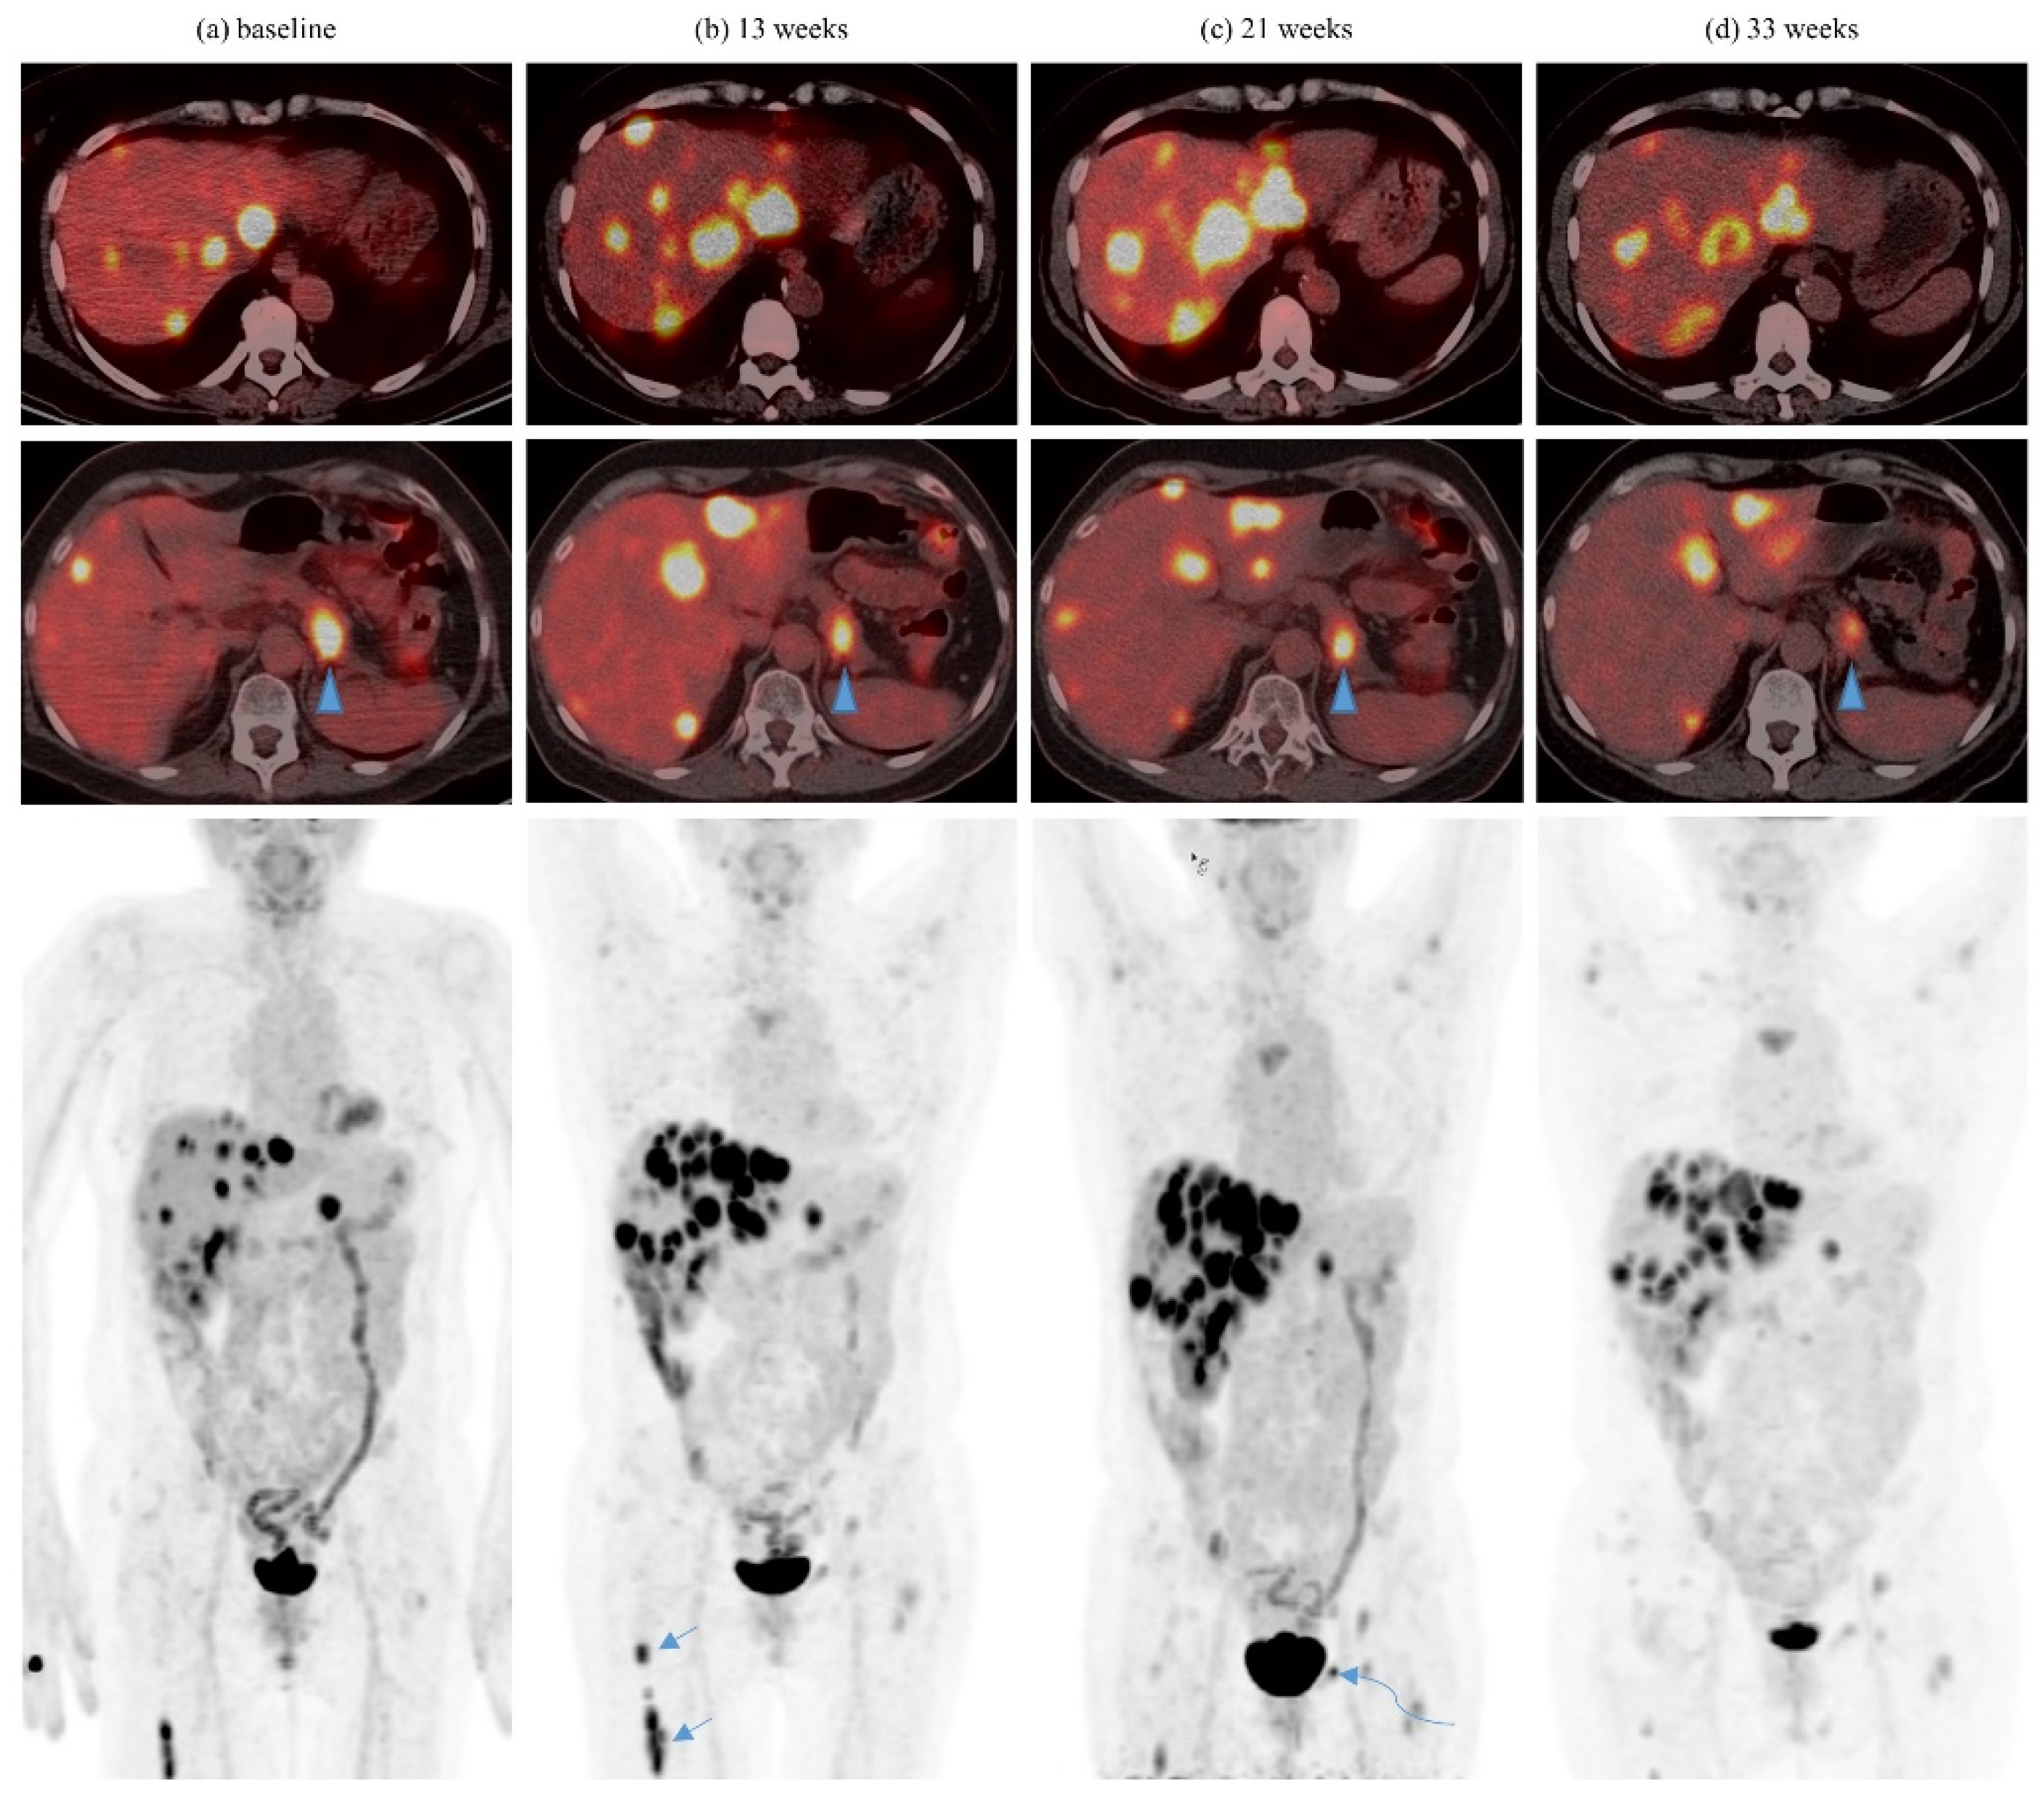

| 5 | Pembrolizumab | 3 6 | 8Gy/1 27Gy/3 | Yes Yes | Femur Pubic bone | Liver, several | 1 | Concurrent axitinib from prior line of treatment maintained |